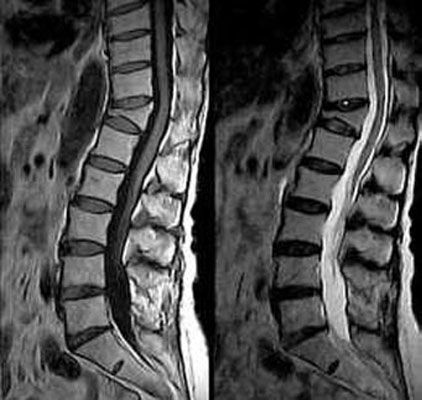

• Κάτω άκρων Power doppler έσω καρωτίδας 3D θυρεοειδούς-πολυοζώδης 3D θυρεοειδούς αδένα Power doppler θυρεοειδούς Triplex φλέβας Triplex καρωτίδας Triplex κοινής καρωτίδας Υπερηχογράφημαμαστού-Ca Υπερηχογράφημα ισχίου-εξάρθρημα 3D εμβρίου